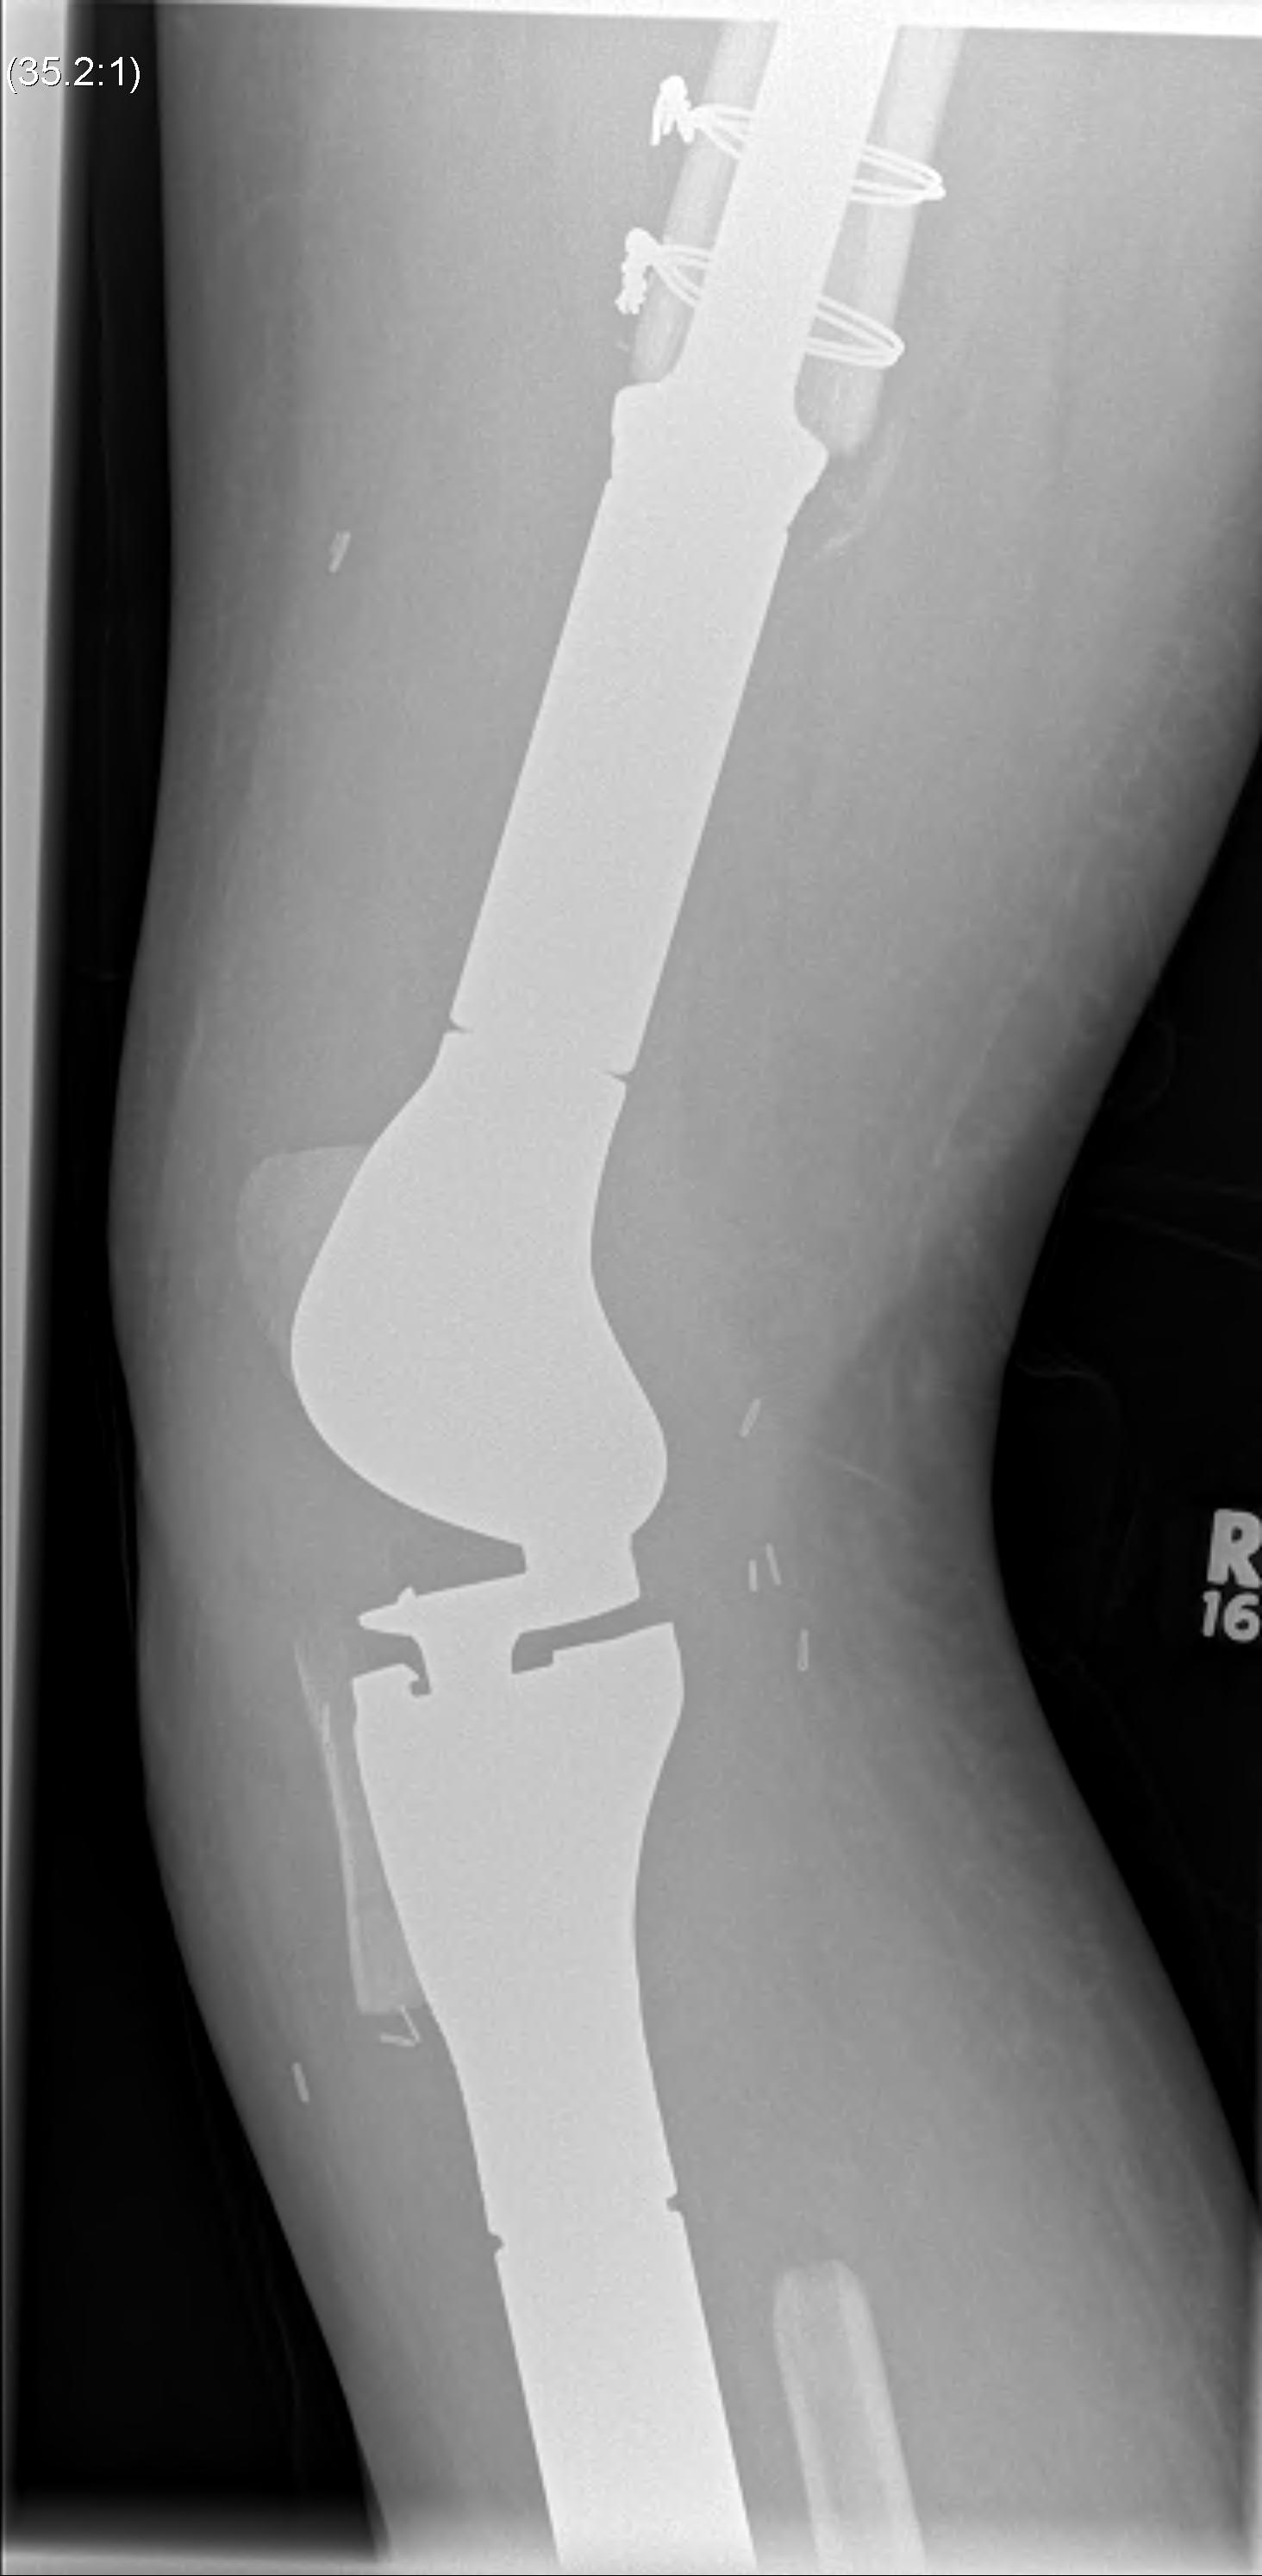

Post distal femoral osteosarcoma resection

Post proximal tibial osteosarcoma resection